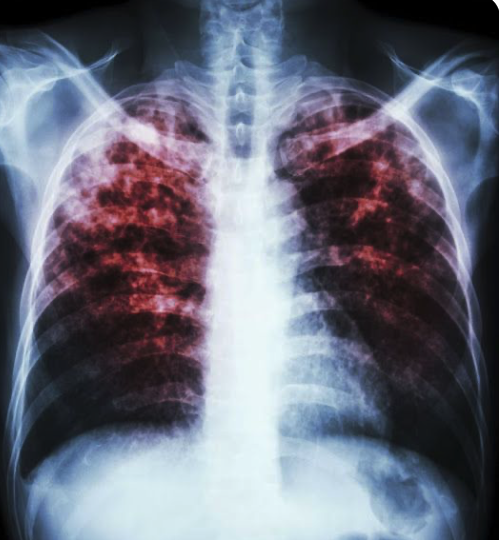

Pour l’année 2025, 516 cas de tuberculose ont été recensés à l’échelle provinciale.

C’est un niveau jugé élevé par les spécialistes et un écart important par rapport aux décennies récentes.

À Montréal, on compte 210 cas, ce qui en fait la région la plus touchée en nombre absolu.

Le Nunavik affiche aussi une situation préoccupante avec 117 cas, malgré une population beaucoup plus restreinte.